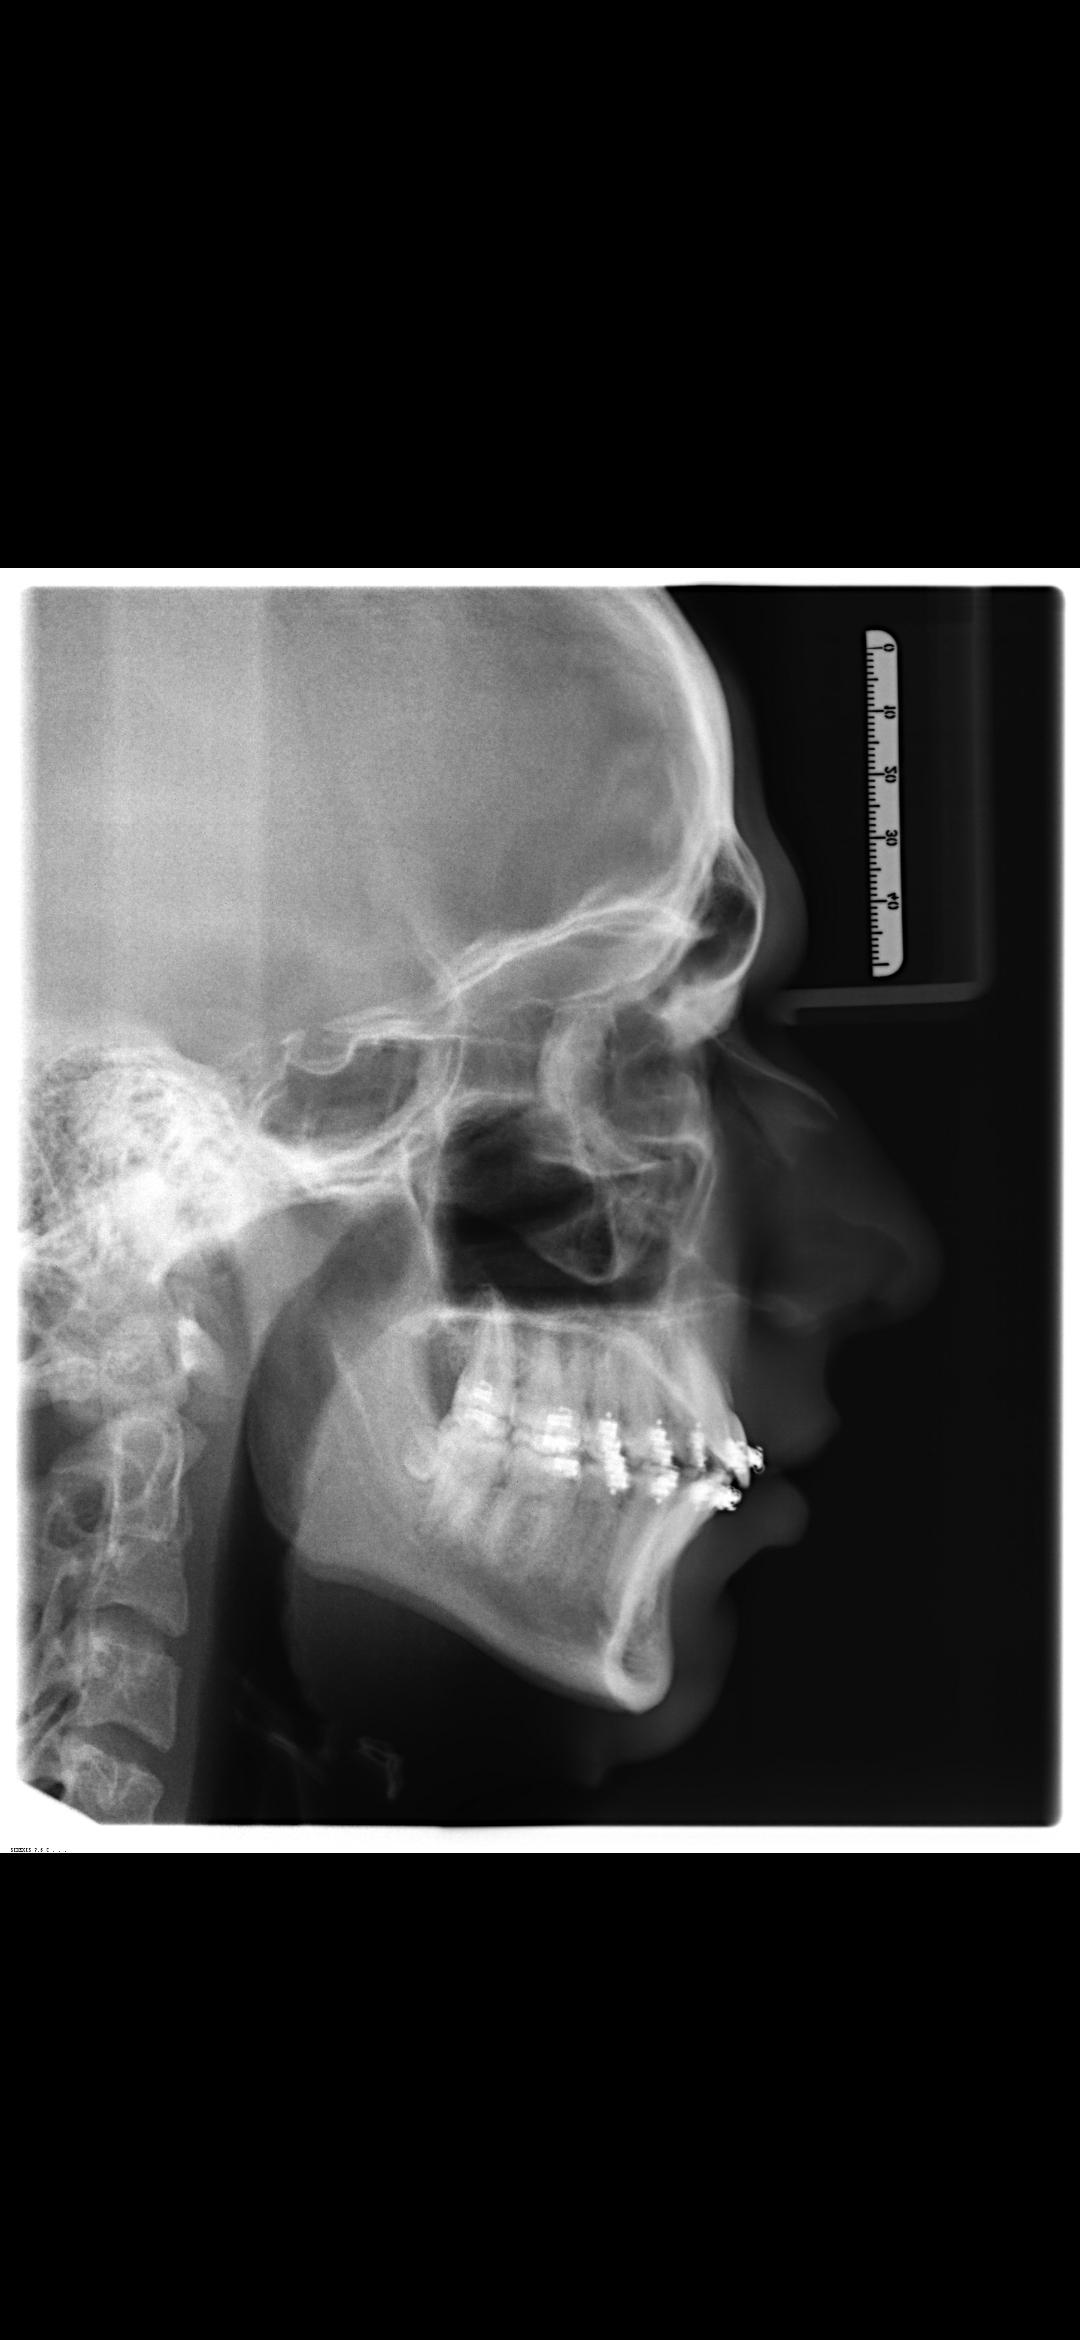

I'm 17, and i'm getting bimax in about 4 weeks. It's for aesthetic purposes and it'll be a bimax + genioplasty and ccw rotation. I'm scared that it'll end up like this:

This is my sub5 side:

This is my sub5 side: